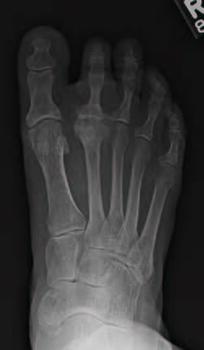

Metatarsal Head Resection. Pan-metatarsal head resection is a common procedure performed in late-stage rheumatoid arthritis; however, singular metatarsal head resection may introduce an increased risk of developing adjunctive pathologies when performed in isolation. This includes transfer metatarsalgia, shortening of the second digit, and even hallux valgus deformity. Adjunctive procedures such as a resection of the base of the proximal phalanx and interpositional arthroplasty following a metatarsal head resection may limit some of the complications seen with isolated metatarsal head resections.16 Singular metatarsal head resections are typically a last resort option in the senior author’s practice (see third photo set above).